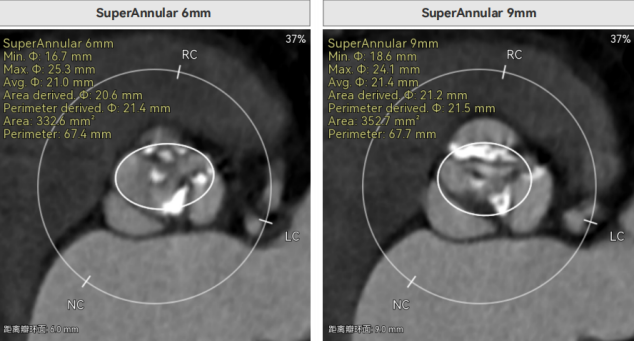

许金鹏教授 安徽省胸科医院 干瓣耐久首选之,15年承诺佑病患:随着病患的复杂性提高及TAVR二次手术窗口期的慢慢到来,摆在临床面前的是如何提升瓣膜使用的耐久性?预装干瓣的获批上市无疑为临床提供了全新的选择。预装干瓣摆脱了传统戊二醛保存的束缚,通过专利抗钙化技术及干式保存工艺打造了一款兼具“曲柔性”和“不沾钙”瓣叶的介入瓣,预期会有更耐久的使用寿命。此次病例患者小瓣环,Prostyle A®自膨瓣的收腰设计,为冠脉开口预留了“生命通道”,而平衡的收腰设计又很好的保证了开口面积,为小瓣环患者血流动力学提供的牢靠的保障。 期待这样一款基于临床需求的性能平衡的耐久干瓣,护佑 TAVR广大患者的全生命周期管理! 患者病史 主要诊断:非风湿性主动脉瓣狭窄(重度);非风湿性主动脉瓣关闭不全(中度);非风湿性二尖瓣关闭不全(中度);心脏扩大(左房明显扩大、左室略大);肺动脉高压(估测肺动脉收缩压约 39mmHg);胸椎压缩性骨折(T9 椎体,考虑新鲜);肺部阴影(两肺慢支改变、多发结节);胆囊术后; 入院检查:BP 109/60mmHg、心率 77 次 / 分(律齐),神清精神可,口唇不绀。 术前超声提示 主动脉瓣钙化并狭窄(重度)伴反流(中量),Vmax509cm/s,PGmax105mmHg;升主动脉增宽;左房明显增大,左室略大;二尖瓣关闭不全伴反流(中+量);瓣尖轻微增厚;室间隔增厚; 术前CT 三叶瓣(L-N融合,功能型二叶瓣),瓣叶增厚中度钙化,钙化主要分布在左冠窦瓣叶边缘及左无融合处、右冠瓣叶基底及边缘,主动脉瓣环径22.2mm,LVOT21.1mm,呈略直通型;双侧冠脉开口高度可,窦部空间大,VTC距离够,预估冠脉低风险,STJ、升主动脉内径可;左室内径可,主动脉水平夹角47°,非横位心。主动脉弓角弓距可;外周入路无明显迂曲,无钙化,两侧股动脉内径可,均可通过20F大鞘,右股低分叉。 手术策略 推荐右侧股动脉为主入路,左侧股动脉为辅助入路,使用20F大鞘,右股分叉上方1cm穿刺。推荐选择AV23瓣膜,18mm球囊预扩,最终理想位置瓣下2mm。 手术过程 在右股动脉穿刺建立通路后,顺利送入大鞘,经食道超声及血管造影确认路径稳定。18mm球囊预扩后评估冠脉灌注良好,后将Prostyle A® AV23瓣膜精准释放于目标位置,超声显示无瓣周漏,术后即刻造影显示无明显反流,导管测平均跨瓣压差8mmHg,心功能明显改善,患者生命体征平稳。 主动脉根部造影 18号球囊预扩 输送器顺利过弓 迅速锚定,平稳释放至工作位 最终造影,位置形态良好,无瓣周漏 Prostyle A®预装干瓣——助力临床最优化解决方案 预装干瓣 便捷顺安:金仕生物专利抗钙化技术运用纳米技术去除组织内的细胞碎片和磷脂,封闭游离醛基,从根本上阻断了瓣膜钙化的多项因素,显著提升了瓣膜的耐久性;同时,相比较传统戊二醛保存方式,干式存储最大限度的保留心包的亲水亲油平衡,还原组织天然曲柔性,进一步保障了瓣叶开合,保证长期耐久性; 流入端桶状设计:流入端桶状的设计,迅速稳定锚定,减少手术时间的同时进一步保障了术中安全; 平衡的收腰设计:该病例左冠高度10.8mm,AV23瓣膜的平衡收腰设计既确保了冠脉开口安全性,又保证了EOA,有效降低了循环崩溃风险,而术后8mmHg的压差的表现更加证明了优秀的血流动力学,进一步提高了瓣膜的耐久性。 专家简介 许金鹏 安徽省胸科医院(点击查看专家详细简历) · END ·